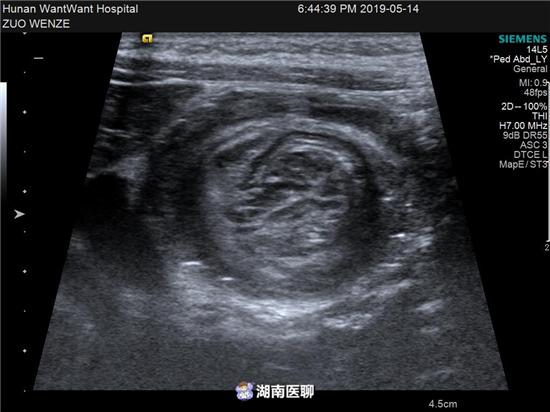

肠套叠则表现为直径为为28mm-35mm的同心圆征,套入长度常大于4cm,肠管蠕动减弱或消失,当套入较深、病程较长时肠壁可出现水肿。

(图为B超下发现的肠套叠)